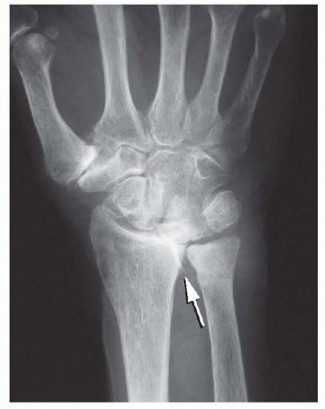

Concurrently, this synovial hypertrophy destabilizes critical ligamentous restraints, most notably the radioulnar ligaments and the triangular fibrocartilage complex (TFCC). This destabilization precipitates joint dislocation or subluxation, creating a harsh biomechanical environment. The classic dorsal manifestation is the Vaughan-Jackson syndrome, also known as caput ulnae syndrome. In this cascade, the distal radioulnar joint (DRUJ) becomes unstable, allowing the distal ulna to subluxate dorsally. The exposed, eroded ulnar head acts as a serrated osteophyte, mechanically grinding through the overlying joint capsule and subsequently the extensor tendons. Because of the anatomical proximity, the extensor digiti quinti (EDQ) is typically the first to succumb to this attritional wear. As the carpus supinates and subluxates volarly over time, the dorsal prominence of the ulna is accentuated, leading to a sequential, ulnar-to-radial rupture pattern involving the extensor digitorum communis (EDC) to the small, ring, and occasionally long fingers.

Addressing the underlying skeletal pathology is the most critical step in preventing re-rupture. The prominent, eroded ulnar head (caput ulnae) must be managed. The dorsal capsule of the DRUJ is opened.

In older, lower-demand patients with severe destruction, a Darrach procedure (resection of the distal ulna) is performed. The distal ulna is transected approximately 1.5 to 2.0 cm proximal to the articular surface using an oscillating saw.

The ulnar stump is smoothed with a rongeur and rasp to ensure no sharp edges remain. To prevent painful radioulnar impingement (ulnar stump instability), the volar capsule and the pronator quadratus are mobilized and sutured dorsally over the resected stump.